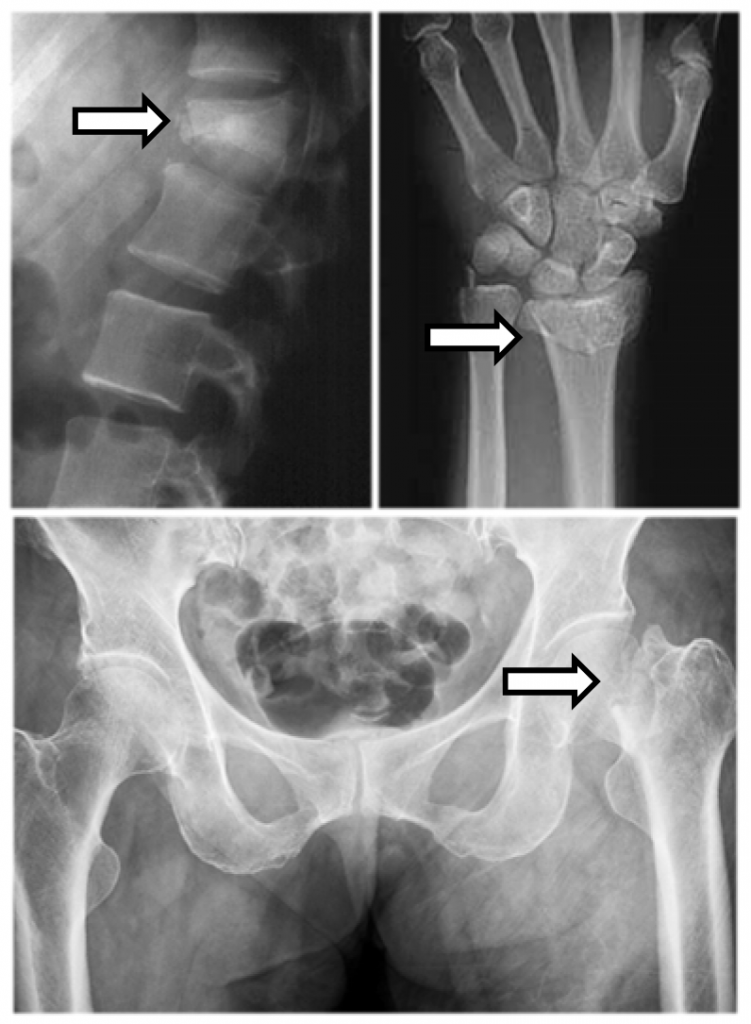

คือภาวะที่ความหนาแน่นของกระดูกลดลง และโครงสร้างของกระดูกเสื่อมลง ทําให้กระดูก เปราะบาง และมีโอกาสหักหรือยุบตัวได้ง่าย พบบ่อยในผู้สูงอายุหรือหญิงวัยหมดประจําเดือน

บริเวณกระดูกสะโพกและกระดูกสันหลัง

ภาวะแทรกซ้อนที่อันตรายที่สุดคือกระดูกหัก บริเวณที่พบบ่อย ได้แก่ กระดูกสันหลัง สะโพก และข้อมือ กระดูกหักจะทําให้เกิดอาการปวดมากจนไม่สามารถใช้งานต่อได้ ต้องพัก รักษาตัวเป็นเวลานานทําให้เกิดภาวะแทรกซ้อนต่างๆ เช่น ติดเชื้อในทางเดินปัสสาวะ ปอด อักเสบ แผลกดทับ ภาวะโรคหัวใจและหลอดเลือด เป็นเหตุให้สุขภาพแย่ลงอย่างรวดเร็ว อาจ เป็นอันตรายต่อชีวิตได้

ระยะแรกมักไม่มีอาการ แต่เมื่อเป็นมากขึ้นอาจมีอาการปวดหลังเรื้อรัง หลังโก่งค่อม ความสูง ลดลง กระดูกหักง่ายกว่าคนปกติแม้ไม่มีอุบัติเหตุที่รุนแรง

จากการยุบตัวของกระดูกสันหลัง